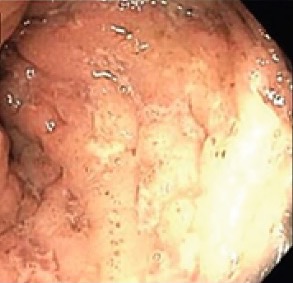

A 23-year-old white man presented to the emergency department with nonradiating epigastric abdominal pain accompanied by nausea and vomiting for 2 to 3 days.

<p>Inflammatory bowel disease (IBD) encompasses a variety of clinical signs and symptoms, and the diagnosis is made with a combination of modalities, including radiographic, endoscopic, and pathologic...